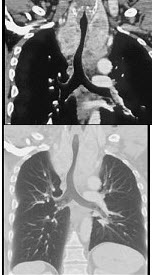

女,52岁,曾患有鼻窦炎,最近发现咳嗽发热,影像学检查如图,最可能的诊断为()

A.多发性肺脓肿

B.浸润型肺结核并空洞形成

C.韦格肉芽肿

D.结节病

E.肺转移瘤